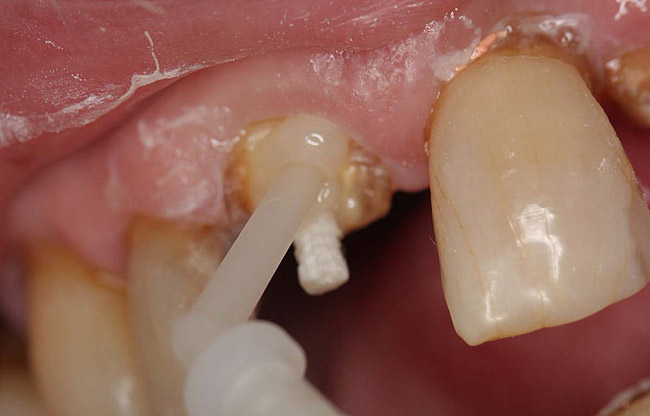

Case 4

A terminally ill patient presented an abscess on the maxillary right central incisor. Endodontic treatment was completed with a composite restoration placed to restore the access hole. The crown fractured off within 1 week (Figure 15 and Figure 16). Gutta-percha was removed, and the canal prepared to accept a C-1 white post (Figure 17). The root was bonded with BRUSH and BOND™ (Parkell, www.parkell.com) and the post was cemented with a resin cement (Figure 18). Absolute Dentin core build-up material was applied (Figure 19). There are many different build-up materials, including glass ionomers such as Ketac-Silver™ (3M ESPE, www.3mespe.com) or Miracle Mix® (GC America, www.gcamerica.com), pastes that are mixed such as Zenith (Carson Dental, www.carsondental.com), and automix syringes such as Absolute Dentin. The material was of a consistency that allows placement without sagging or running (Figure 20). It was light-cured and prepared for temporization (Figure 21) and the final all-composite restoration was delivered (Figure 22).

Figure 17  The root canal was prepared to accept a post.

Figure 17

Figure 18  The post was cemented with bonded resin cement.

Figure 18